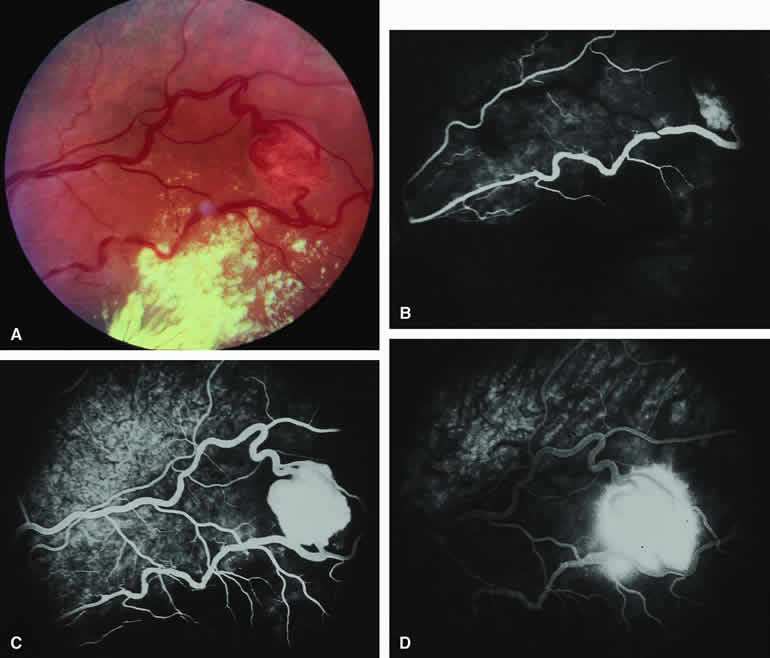

Choroidal Nevus Versus Melanoma with Choroidal Neovascular Membrane

A choroidal neovascular membrane occasionally develops from the surface of a small melanocytic choroidal tumor (nevus versus melanoma).12 This vascular structure can usually be anticipated because of the presence of ophthalmoscopically evident hemorrhagic or exudative subretinal fluid overlying a portion of the tumor (Fig. 8A). Fluorescein angiography in such cases (see Fig. 8B to D) generally reveals the neovascular membrane as a relatively well-defined vascular network that fluoresces brightly in the early frames of the study and leaks progressively by the late frames. If the subretinal fluid is grossly hemorrhagic, ICG angiographymay show the choroidal neovascular network better than does fluorescein angiography.